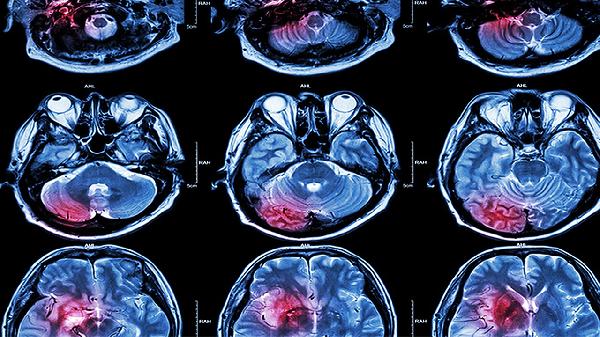

脑积水、脑白质病变等器质性疾病可能导致持续性慢波,常伴有运动障碍、语言退化等表现。头部MRI检查可明确病变位置与程度,需神经科介入治疗。